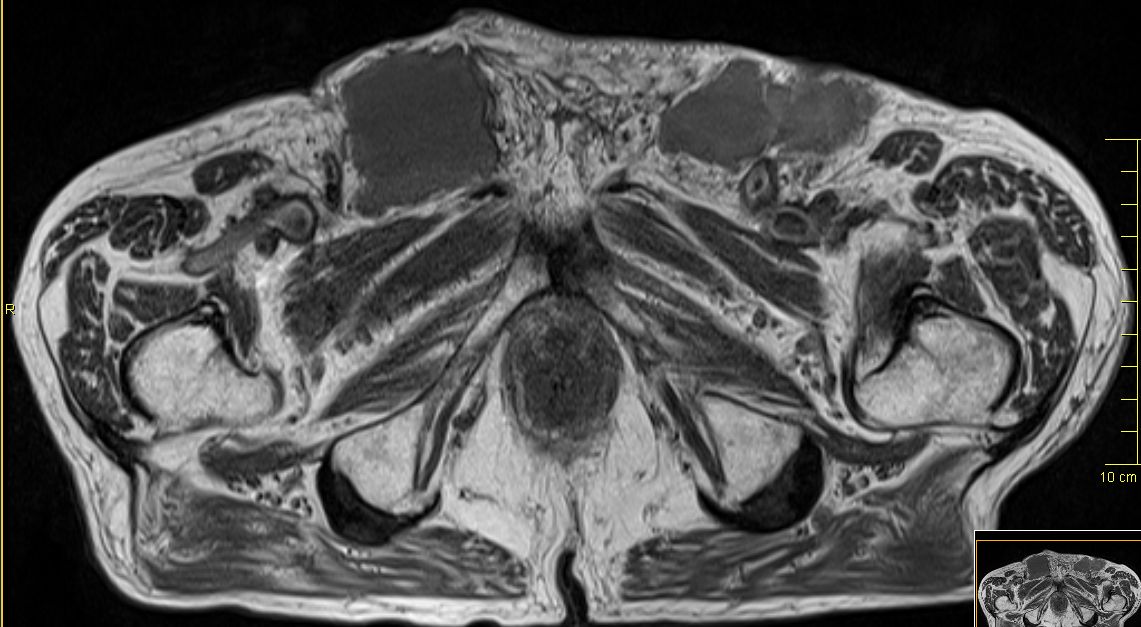

Lymphknotenmetastasen bei Peniskarzinom

95-jähriger Mann, beim vor 9 Monaten ein Plattenepithelkarzinom der Vorhaut entfernt wurde. Jetzt in beiden Leisten faustgroße, zentral zystisch zerfallende Lymphknotenpakete.